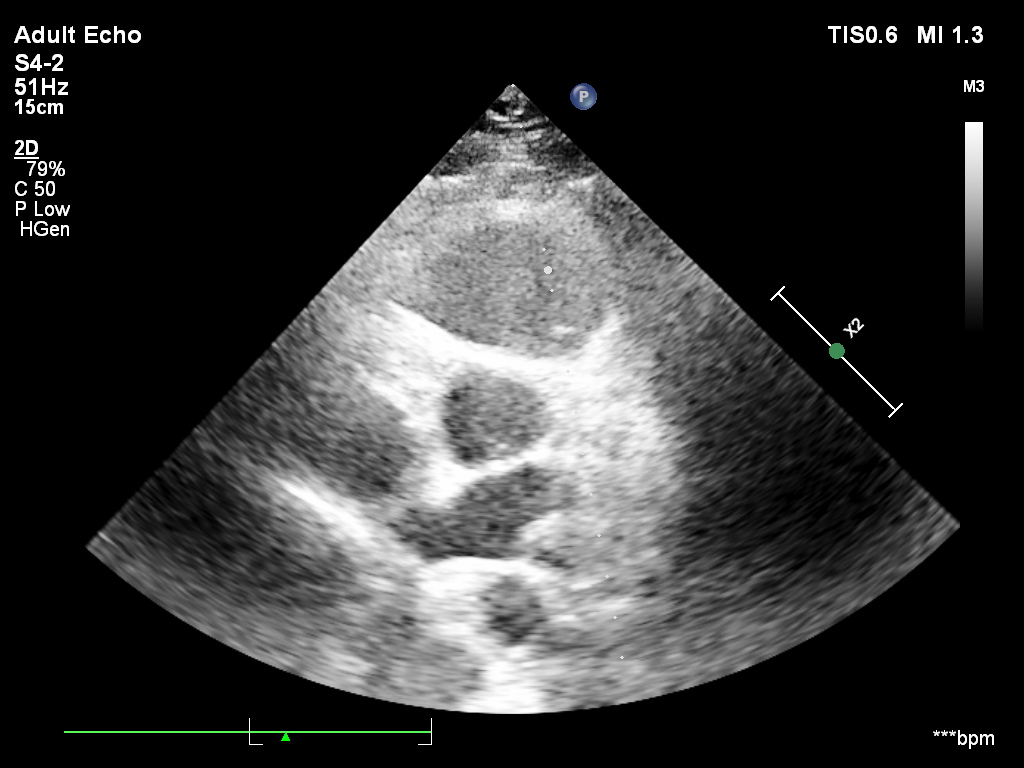

Przypadek 3.A

W trzecim – warunki obrazowania są trudne i nawet przy podejrzeniu BAV potwierdzenie diagnozy może być niepewne.

In the third, imaging conditions are very challenging, and even if BAV is suspected, confirmation may be uncertain.